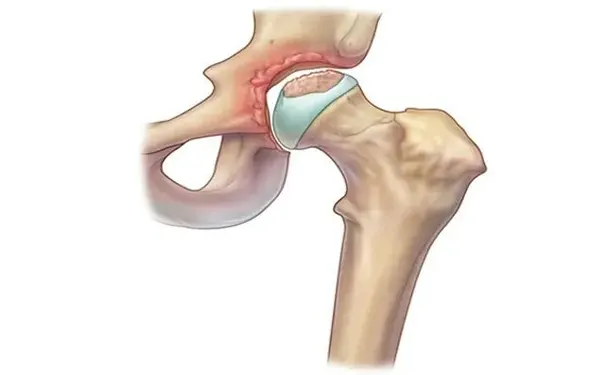

股骨头坏死被称为 “不死癌症”,其主要成因是股骨头细胞缺乏充足的血液循环与养分供应,进而发生坏死、坍塌,不仅会损害关节功能,还会严重影响日常活动,如同木头被蛀蚀后无法承受重量。

股骨头坏死病程进展迅速,越早治疗治愈率越高。多数患者就医时已出现股骨头大范围坏死,若未能及时干预,90% 的患者病情会持续恶化,最终导致髋关节严重受损,需通过人工髋关节置换手术恢复行动力。